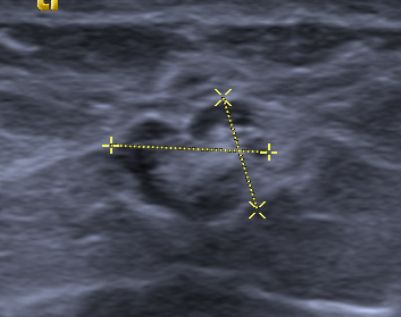

intramammärer Lymphknoten 45-jährige Frau Bei einem ausgedehnten, wohl multizentrischen Mammakarzinom der rechten Brust mit axillären Lymphknotenmetastasen (Zustand nach Sentinel-Node-Biopsie rechts und Portimplantation links) wurde im auswärtigen Kernspintomogramm eine kleine kontrastanreichernde oberflächliche Läsion in der linken Mamma bei 2 Uhr links gesehen. Weitere Diagnostik bzw. Abklärung erbeten. In Kenntnis der Kernspintomographie lässt sich in einer Tiefe von 5 mm ab dem Hautniveau peripher links bei 2 Uhr in einem Abstand von 8 cm ein bohnenartig konfigurierter Herdbefund mit einem kapselartigen echoarmen Randsaum, glatten Außengrenzen und einem echoreichen zentralen Reflex darstellen. Die Größe des Befundes beträgt 8,4 x 7,4 x 4,6 mm. In der farbcodierten Duplexsonographie lassen sich kräftige, bis zum Zentrum des Areales ziehende Gefäße sowie kleinere zentrale Gefäße in der echoreichen Struktur nachweisen. Sonomorphologisch entspricht der Befund einem typischen intramammären Lymphknoten. Weitere echomorphologisch vergleichbare Lymphknoten lassen sich axillär in einer maximalen Länge von 11,5 mm auf der linken Seite nachweisen.